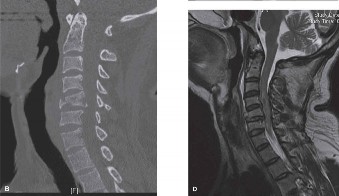

When surgical intervention becomes unavoidable, meticulous pre-operative planning is the cornerstone of a successful outcome. Advanced imaging is non-negotiable. An MRI with and without gadolinium contrast is the gold standard for defining the extent of the epidural abscess, the degree of neural compression, and the involvement of adjacent paraspinal musculature (e.g., psoas abscess). T1-weighted images typically show hypointense signals in the infected marrow, while T2-weighted and STIR sequences reveal hyperintense fluid and edema in the disc space and vertebral bodies. Gadolinium enhancement highlights the vascularized inflammatory phlegmon and the capsule of any abscesses.

In addition to MRI, a fine-cut computed tomography (CT) scan is essential for evaluating bony destruction. CT allows the surgeon to assess bone stock for pedicle screw purchase and to template the size of the interbody cages required for anterior column reconstruction. Upright standing radiographs (if the patient can tolerate them) or full-length supine films are necessary to evaluate global spinal alignment and regional kyphosis.

The surgical strategy for lumbar spondylodiscitis typically involves radical debridement of the infected tissue, decompression of the neural elements, and rigid mechanical stabilization. While combined anterior-posterior approaches were historically the gold standard, modern spinal instrumentation and techniques have made posterior-only approaches highly effective for the majority of cases, particularly in the mid-to-lower lumbar spine.

Following debridement, a large void is left in the anterior column. To restore disc height, correct kyphosis, and provide structural support, an interbody device must be inserted. Historically, autologous tricortical iliac crest bone graft was the gold standard. However, structural allografts and titanium cages have been proven safe and highly effective even in the setting of active pyogenic infection, provided that the debridement is thorough and the patient is maintained on appropriate culture-directed antibiotics.

Titanium is particularly advantageous as it resists bacterial colonization better than stainless steel and provides excellent immediate structural support. The cage is packed with autograft (harvested from the laminectomy or iliac crest) or advanced osteoconductive matrices. Once the cage is impacted into the disc space, the pedicle screws are connected with titanium rods, and compression is applied across the construct to lock the interbody graft in place and restore lumbar lordosis. A posterolateral decortication and fusion are then performed using remaining bone graft.

Surgically, landmark biomechanical and clinical studies over the past decade have revolutionized the approach to anterior column reconstruction in the setting of infection. Historically, the use of metallic implants in an infected field was considered taboo. However, extensive retrospective and prospective cohorts have now definitively shown that titanium interbody cages can be safely placed into an actively infected disc space following radical debridement. Titanium's ability to integrate with host bone and its resistance to biofilm formation make it a superior alternative to structural allograft, which carries a higher risk of serving as a necrotic nidus for persistent infection.